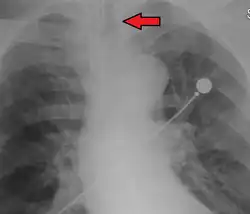

Idealmente, al menos uno de los métodos utilizados para confirmar la colocación del tubo traqueal será un instrumento de medición. La capnografía de forma de onda ha surgido como el estándar de oro para la confirmación de la colocación del tubo dentro de la tráquea. Otros métodos que dependen de instrumentos incluyen el uso de un detector colorimétrico de dióxido de carbono al final de la espiración, un bulbo esofágico autoinflable o un dispositivo de detección esofágica.[35] La punta distal de un tubo traqueal correctamente posicionado estará ubicada en la mitad de la tráquea, aproximadamente 2 cm (1 plg) por encima de la bifurcación de la carina; esto puede confirmarse mediante una radiografía de tórax. Si se inserta demasiado dentro de la tráquea (más allá de la carina), es probable que la punta del tubo traqueal esté dentro del bronquio principal derecho, una situación a menudo referida como "intubación del bronquio principal derecho". En esta situación, el pulmón izquierdo puede no participar en la ventilación, lo que puede llevar a una disminución del contenido de oxígeno debido a una desigualdad ventilación-perfusión.[36]

La punta de un tubo traqueal correctamente posicionado estará en la mitad de la tráquea, entre las clavículas en una radiografía de tórax anteroposterior. El diámetro correcto del tubo es aquel que resulta en una fuga pequeña a una presión de aproximadamente 25 cm de agua. El diámetro interno apropiado del tubo endotraqueal se estima como aproximadamente el mismo diámetro que el dedo meñique del niño. La longitud adecuada del tubo endotraqueal puede estimarse duplicando la distancia desde la comisura de la boca del niño hasta el canal auditivo. Para bebés prematuros, un diámetro interno de 2.5 mm es apropiado. Para bebés de edad gestacional a término, un diámetro interno de 3 mm es adecuado. Para niños de 1 año o más con nutrición normal, se utilizan dos fórmulas para estimar el diámetro interno y la profundidad de inserción del tubo: el diámetro interno en mm es (edad en años + 16) / 4, mientras que la profundidad de inserción en cm es 12 + (edad en años / 2).[33]